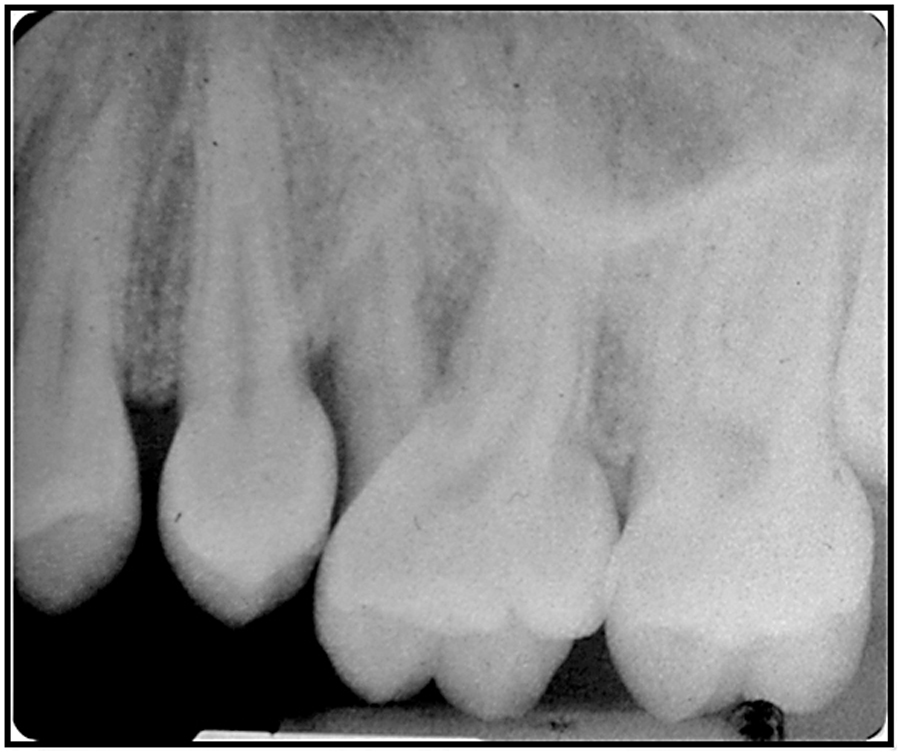

INTRODUCTIONThe main cause for tooth loss today is periodontitis. It predominantly strikes the over 40-year-old age group. Prevention of periodontitis is imperative to general and oral health with the population becoming progressively older.31 Periodontal patients can benefit from the additional data that user-friendly chair side microbiological culture and sensitivity testing provides to augment conventional periodontal … Read more